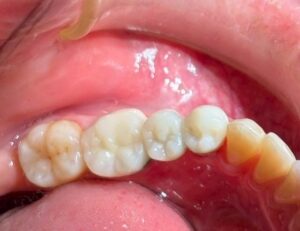

私は ブリッジ修復 を 選択しました。

歯科技工 は モチロン  石三くん です。

違和感ない 形態で 仮歯を 創って くれました。

基本通り の プレパレーションが デキました。

赤い 部分は グラスアイオノマーセメント です。

裏層 に 私は

コンポジット レジン は 使いません。

また

裏層部分 は 歯冠色 に しません。

ブリッジ修復 の 仮歯を 装着 しました。